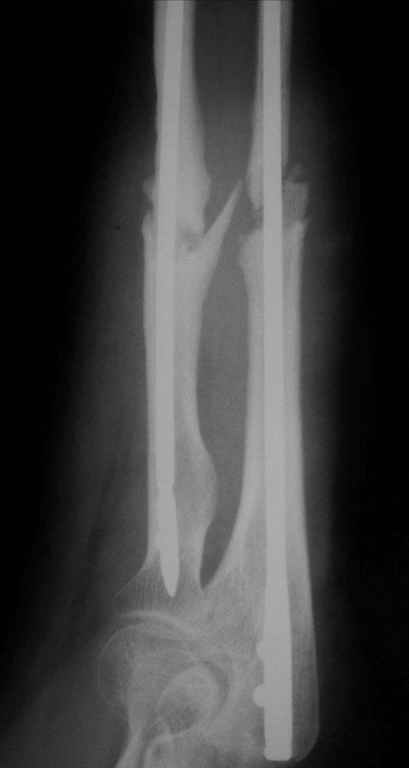

Уважаемые коллеги!У нас в травматологическом отделении клиник кафедры травматологии Самарского медуниверситета находится пациентка с ложными суставами костей предплечья, после остеосинтеза спицами (8 месяцев).

Девушка молодая, аппарат внешней фиксации категорически не приемлет. Выполнен закрытый БИОС СнМ с расверливанием (сверлом 4,5 мм).Хотелось ознакомиться с вашими комментариями.

1.Послеоперационные снимки сделаны на разных уровнях, но в одной проекции. Что во второй?

2.До операции были правильные взаимоотношения в дистальном лучелоктевом сочленении, после - лучевая заметно длиннее.

3.Лучевая кость практически лишена физиологического изгиба. Обусловлено это тем, что стержень не был соответсвующим образом изогнут, и спрямил кость. Даже если ротационные взаимоотношения отломков правильные (что отнюдь не факт), будет ротационная контрактура. Для ориентира, к чему стремиться, стоило бы перед операцией сделать снимок противоположного предплечья в той же проекции - предплечье в нейтральном положении, ладонь вниз, локтвой сустав в профиль.

4.Целесообразность статического запирания гвоздей тут довольно сомнительна, хорошего контакта на стыке не видно, осбенно на локтевой.

Пытались ли дать компрессию, и каким образом?

5.В лучевой кости винты введены в тыльно-ладонном направлении, что подвергало риску сухожилия и сосуды.

6. В дистальном отделе локтевой кости винт раза в два длиннее, чем надо. Как меряете необходимую длину?

Спасибо.